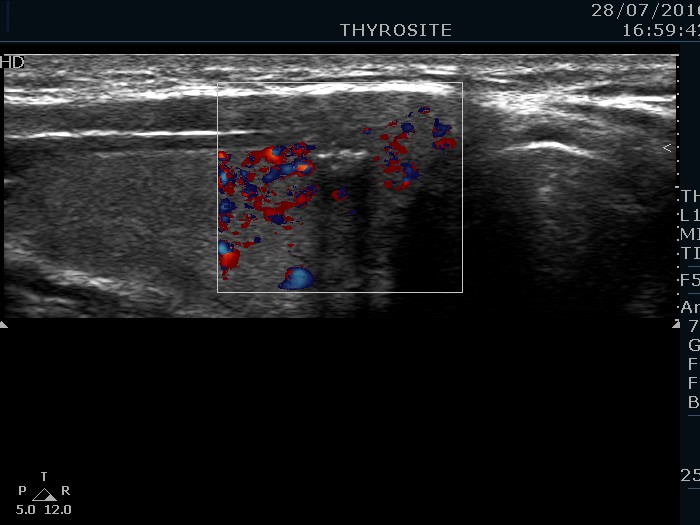

Right lobe, longitudinal scan

Right lobe, longitudinal scan, enlargement, color Doppler mode. The lesion is avascular.